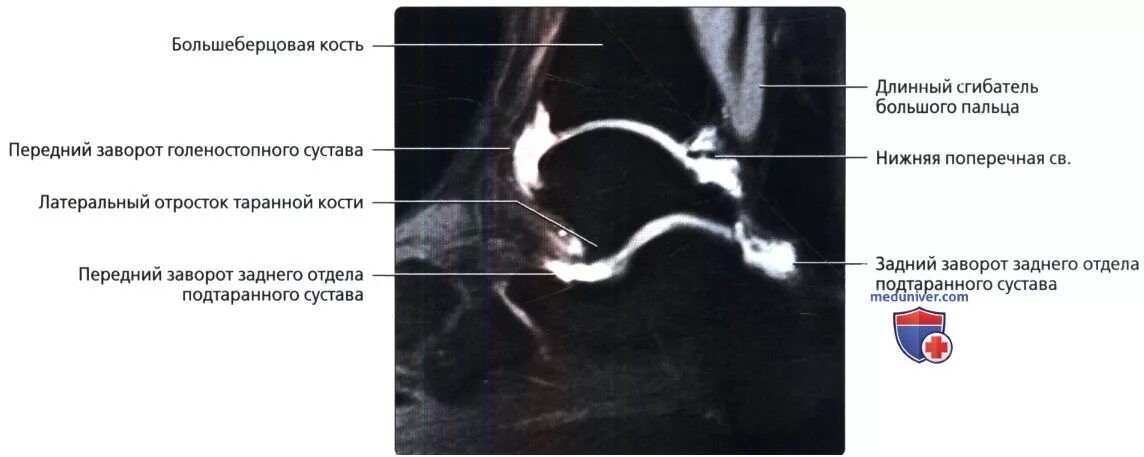

Синовит голеностопного таранного сустава